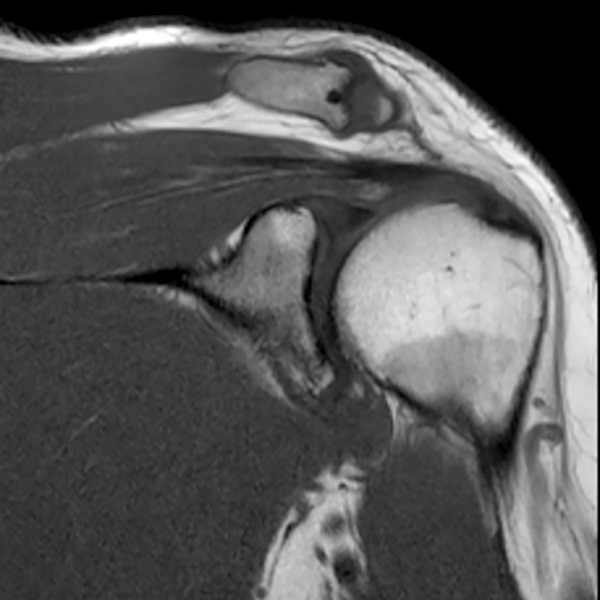

El diagnóstico de la artrosis en el hombro se realiza principalmente a través de la evaluación de los síntomas y un examen físico realizado por un ortopedista. Durante el examen físico, el médico evaluará la movilidad del hombro y buscará signos de inflamación o deformidad. Además, puede solicitar una radiografía para evaluar la estructura del hombro y determinar el grado de la artrosis.